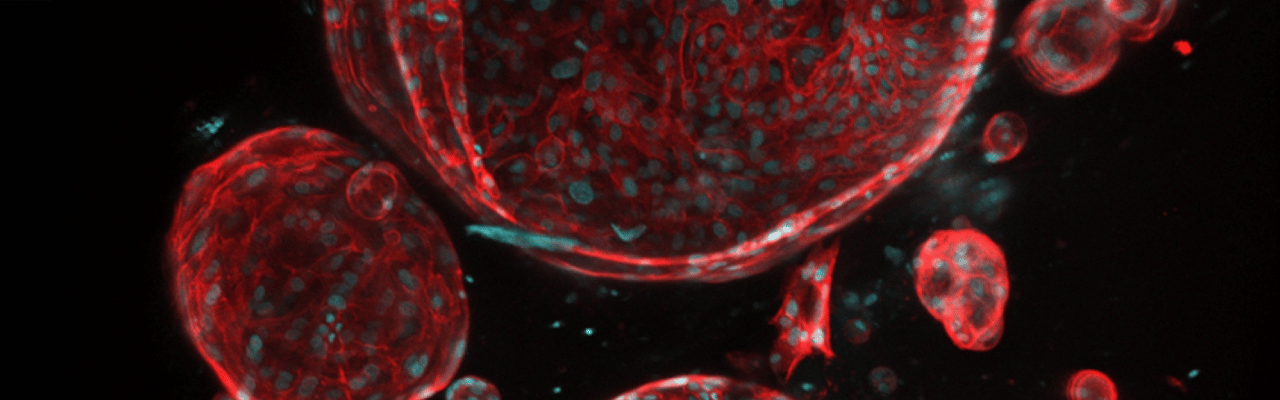

UTSW receives ARPA-H award to create functioning artificial liver

Project that could offer solution to donor organ shortage attracts up to $25 million in funding

UT Southwestern Medical Center has received an award from the Advanced Research Projects Agency for Health (ARPA-H) to develop livers using patients’ own cells and an innovative three-dimensional (3D) printing approach. If successful, this project – known as Vascularized Immunocompetent Tissue as an Alternative Liver (VITAL) – could significantly reduce the gap between supply and demand for donor livers, negate the necessity of lifelong immunosuppression for liver transplant patients, and create artificial livers for in vitro drug testing and research. The project is under ARPA-H’s Personalized Regenerative Immunocompetent Nanotechnology Tissue (PRINT) program, which is led by ARPA-H Program Manager Ryan Spitler, Ph.D.

“Over the last two decades, researchers have made remarkable progress toward the goal of creating lab-made organs, including innovations in biomaterials, stem cell differentiation, and bioprinting. UT Southwestern is an ideal environment to bring together the recent advances that have never been combined before,” said the project’s principal investigator, Muhammad Rizwan, Ph.D., Assistant Professor of Biomedical Engineering and Ophthalmology at UT Southwestern.

Each year, liver cirrhosis and chronic liver diseases cause about 50,000 deaths in the U.S. As of September 2024, nearly 10,000 people were on the waiting list for a donor liver, with wait times averaging about seven months, according to the Health Resources & Services Administration. Statistics show that up to 31% of patients die while waiting for a donor liver.